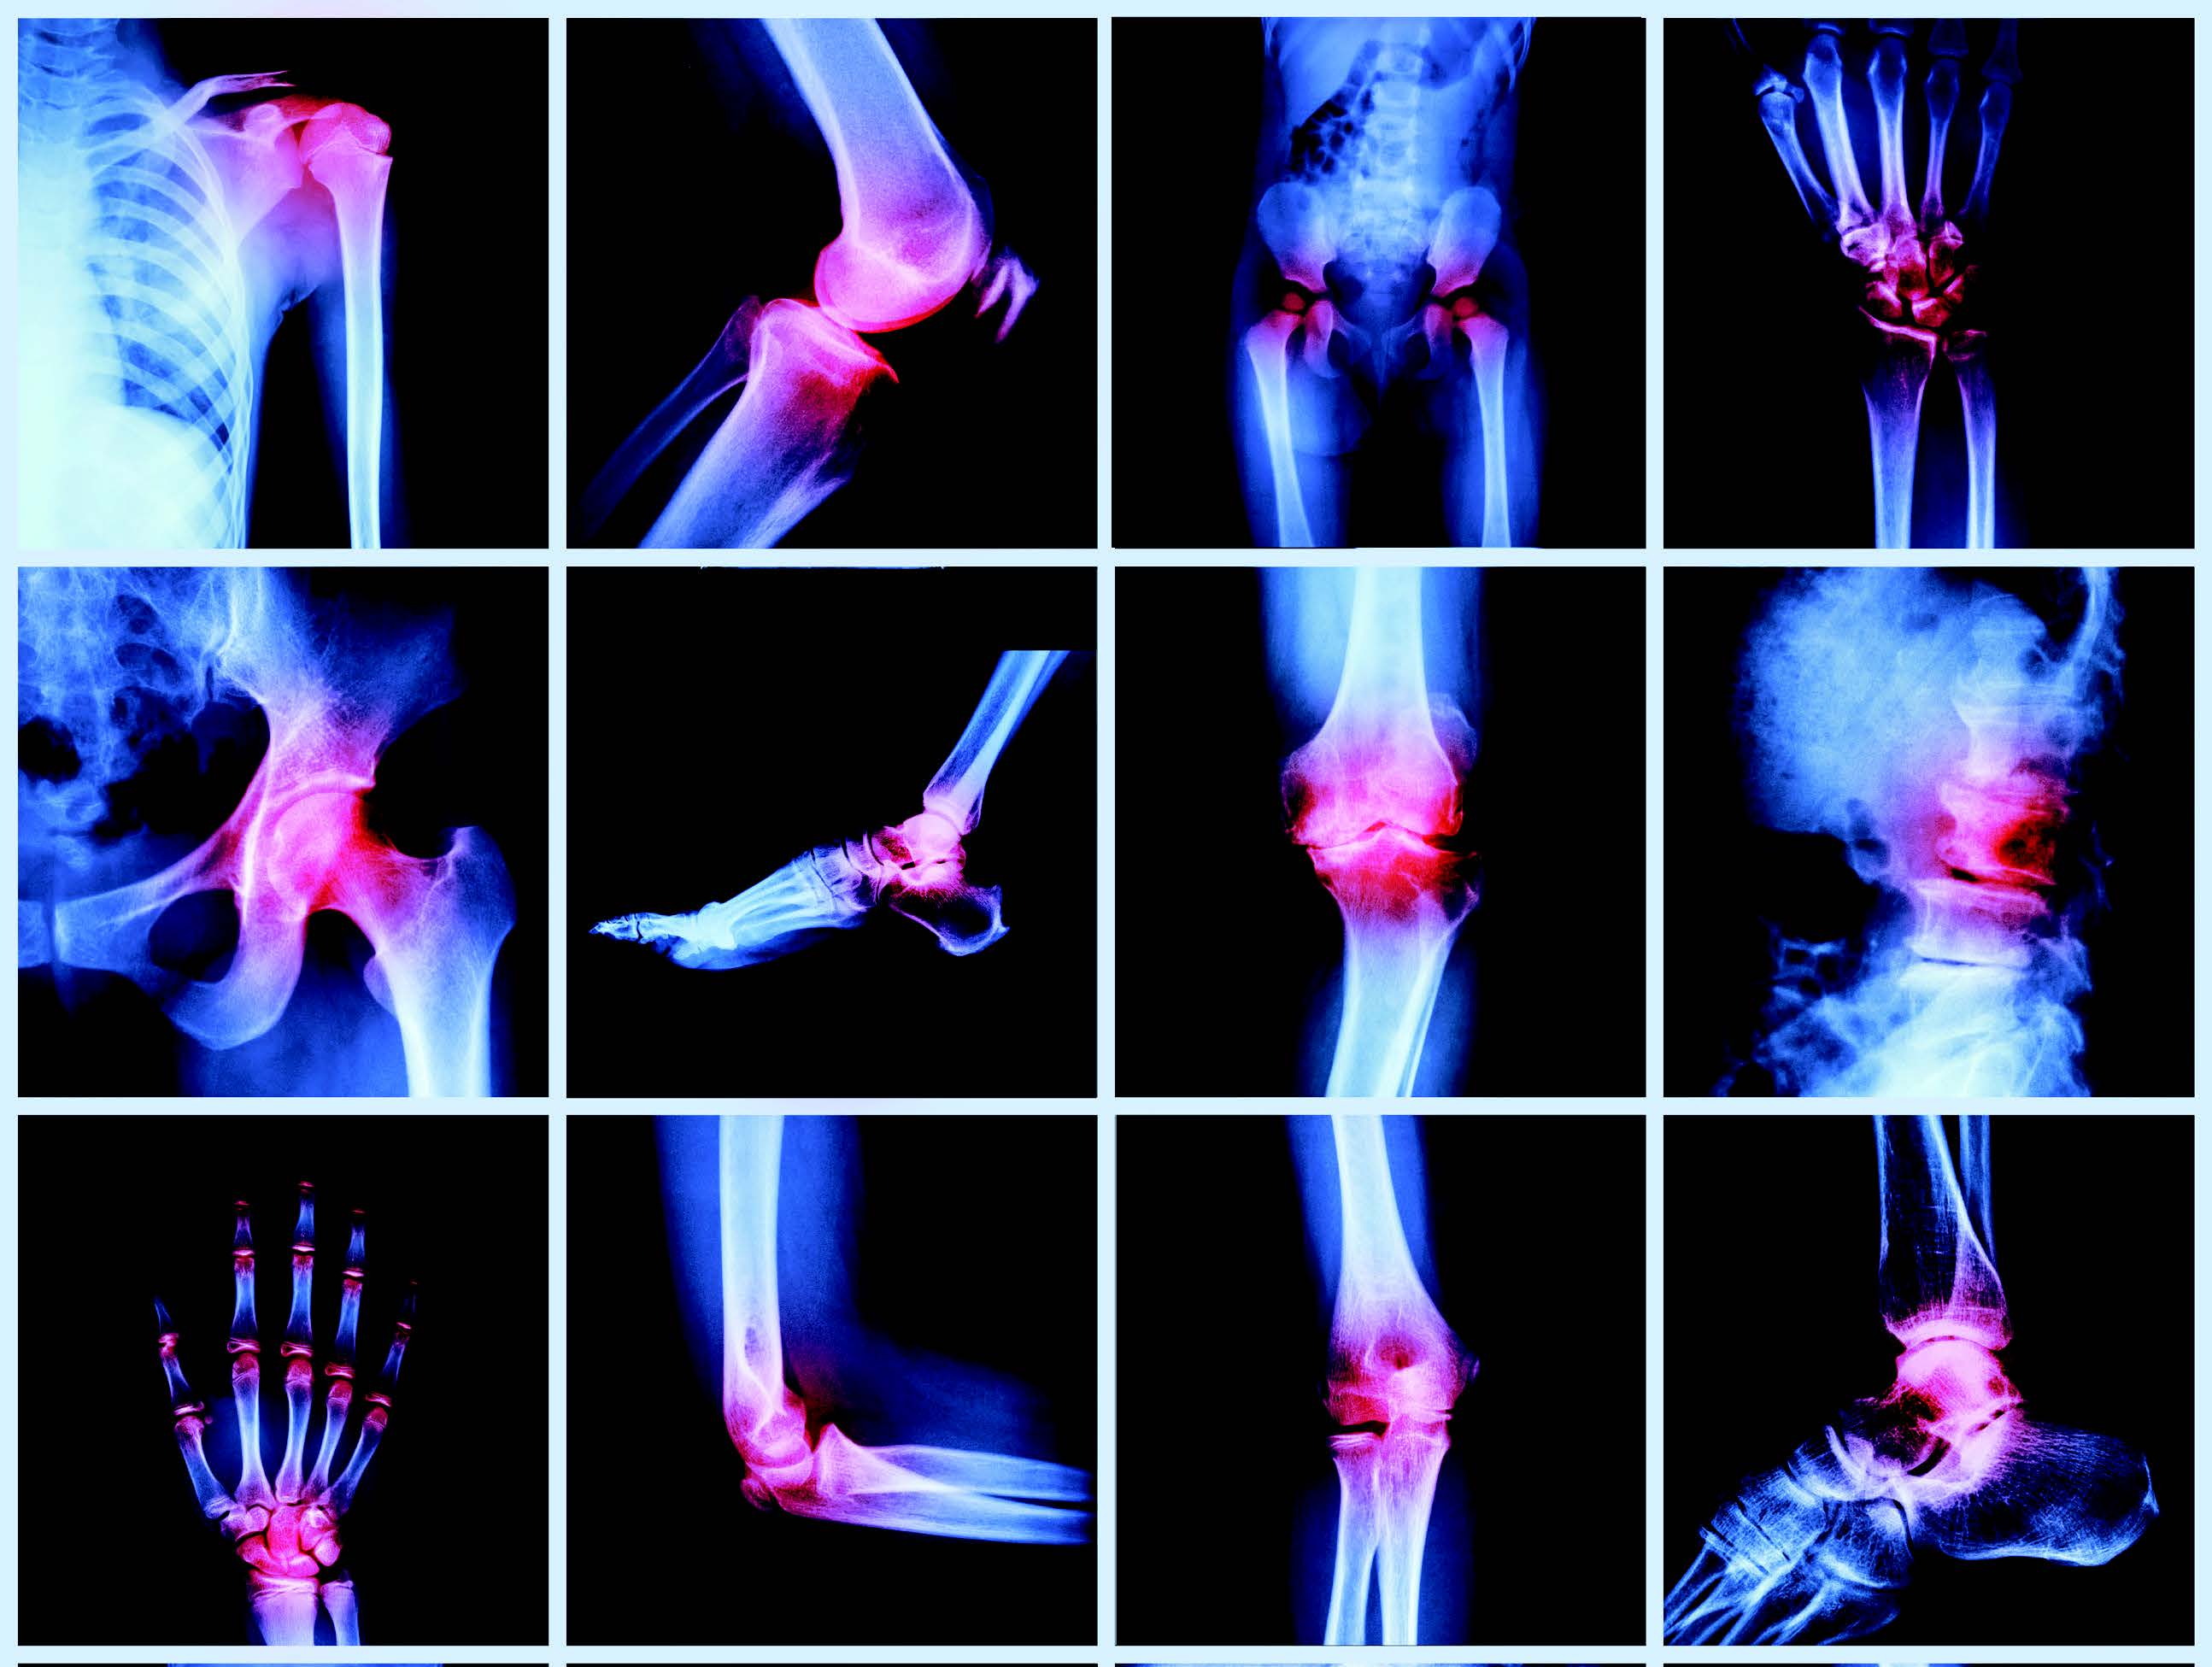

The Veer Hospital provides effective and high-quality healthcare services with 20+ departments, 16 special units and 50+ physicians. We offer an up-to-date medical approach in an ethical and reliable environment. We maintain our reputation in the health sector with our experienced medical staff who continuously improve qualified healthcare with an uncompromising focus when it comes to proficiency and academic values.